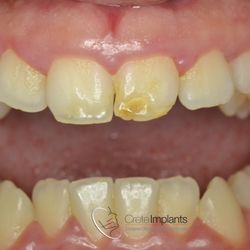

Η νεαρή αυτή ασθενής προσήλθε στο ιατρείο παραπονούμενη για την εμφάνιση των τεσσάρων άνω τομέων της.

Τα δόντια είχαν με την πάροδο των ετών σπάσει στην κοπτική τους επιφάνεια και το φαινόμενο αυτό επιδεινώνονταν σταδιακά με απώλεια όλο και περισσότερης οδοντικής ουσίας.

Αποφασίστηκε να αποκατασταθεί η δομική ακεραιότητα των δοντιών αυτών με χρήση σύνθετης ρητίνης νανουβριδικής τεχνολογίας (Herculite XVR Ultra/Kerr).

Η αποκατάσταση τους έγινε σε ένα ραντεβού και το αισθητικό αποτέλεσμα ικανοποίησε στο ακέραιο τις προσδοκίες της ασθενούς μας.